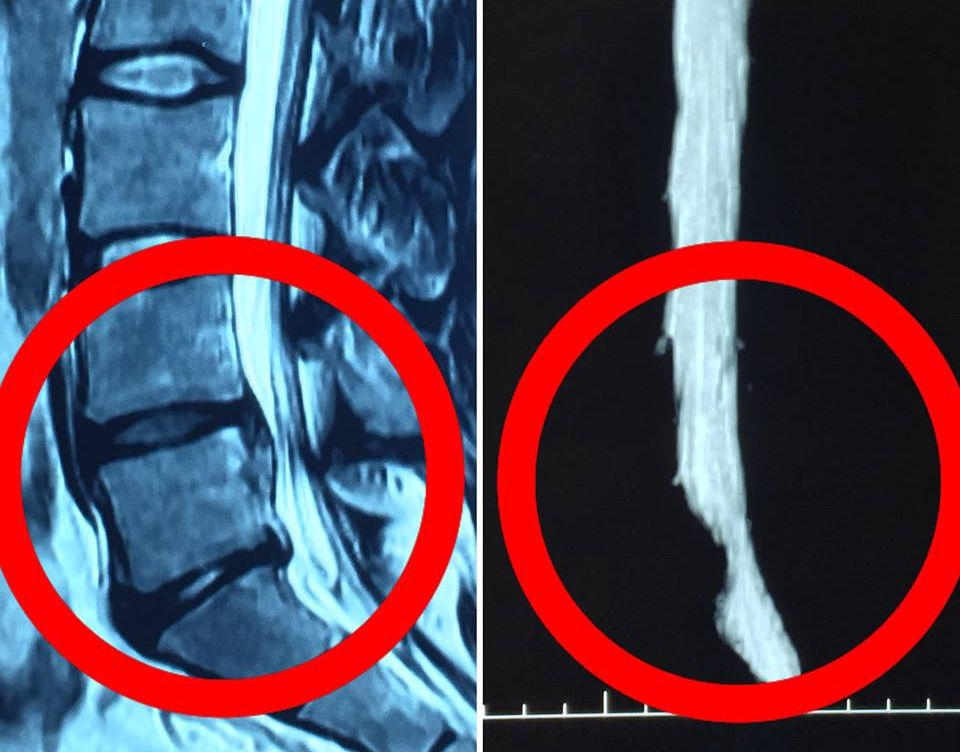

Lumbar Hernia Ultrasound . Abdominal hernias represent common conditions and occur when a structure of the abdominal cavity. the mri protocol for examination of the lumbar spine in patients with symptoms of nerve compression is quite simple. patients with lumbar hernias can present with a variety of symptoms, including a posterolateral mass, back pain,. lumbar hernia has been frequently misdiagnosed as lipomas or. Examples of abdominal wall hernias:. If this diagnosis is suspected, valsalva. timely and accurate diagnosis plays an important role in the later treatment and rehabilitation of ldh. this case shows a superior lumbar hernia on ultrasound as well as mri.